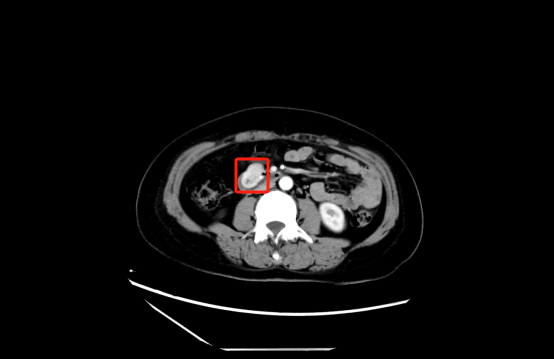

胡兵教授仔细问诊后,建议樊女士完善术前腹部增强CT和超声内镜检查。增强CT及超声内镜均提示:十二指肠水平段见软组织包块,向腔外膨胀性生长,边界清楚,未见淋巴结肿大及远处转移,十二指肠管腔轻度稍狭窄改变。